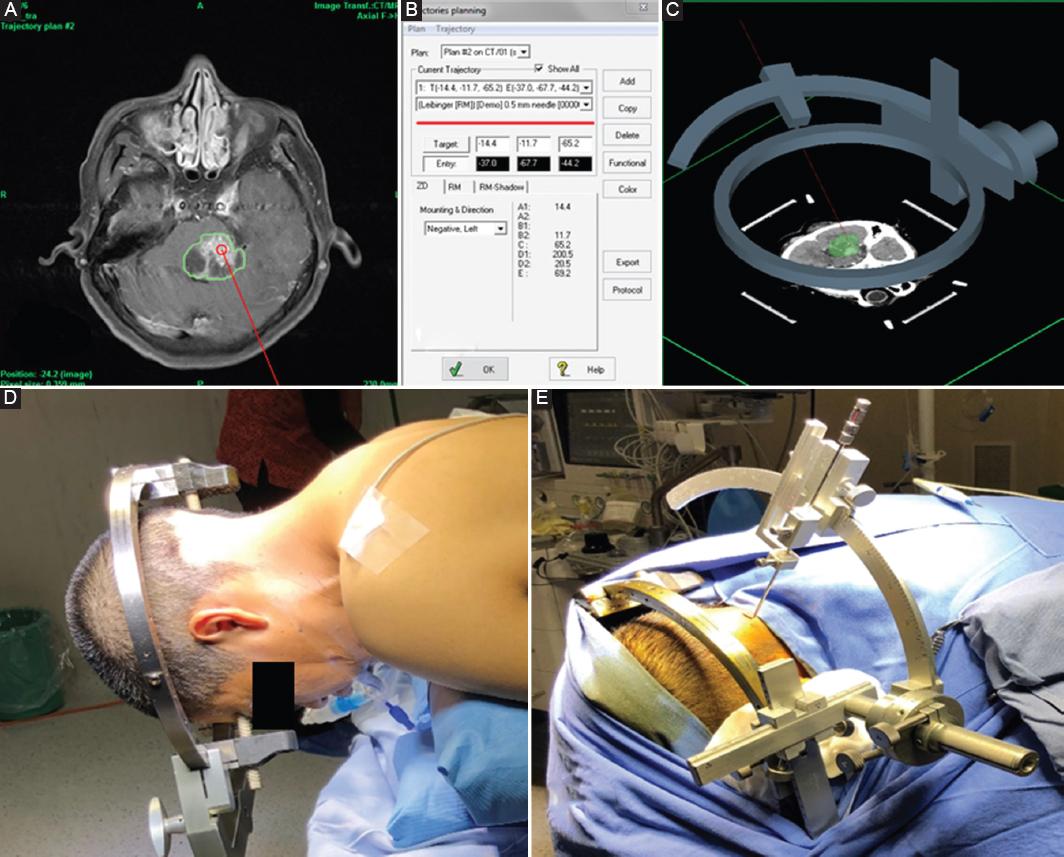

Before performing surgeries, all patients and their caregivers signed an informed consent with approval from the bioethics committee following the 1964 Helsinki Declaration, who had a brain contrast-enhanced T1-weighted MRI, with 1 mm slices (Fig. 1). Under local anesthesia with 2% lidocaine at the site of each pin, the Zamorano-Dujovny stereotactic frame (ZD; FL Fischer, Freiburg, Germany) was placed, aligned to the orbitomeatal line, with its fiduciary system inverted (Fig. 2). Subsequently, a contrast-enhanced head CT was performed, with 2 mm slices without interval, for exportation to Praezis Plus Version 3.1.0.112 software (TatraMed s.r.o., Bratislava, Slovakia) for fusion with MRI, and stereotactic planning of two targets on the lesion, defining trajectories to evade vascular, ventricular or cisternal structures, as well as areas with diffusion restriction because they were considered of poor diagnostic value. Successively, at the operating room, general anesthesia was administered to all patients for prone positioning and head coupled to the fixation device, with the surgical table in the semi-Fowler arrangement. When we treated pediatric patients, the ZD stereotactic frame was placed at the operating room under general anesthesia and endotracheal intubation, to later transfer them to CT, and then return to proceed with SBB. Negative right or left mounting of the stereotactic arch was achieved after verification of pre-established stereotactic coordinates. After the skin incision, an occipital burr-hole was made with a 14 mm auto-stop drill to allow dural opening by monopolar electrosurgery electrode applied to the tip of the Sedan-type biopsy needle (FL Fischer, Freiburg, Germany) to prevent cerebrospinal fluid (CSF) drainage that could cause brain shift (Fig. 3). Through a transcerebellar-transpeduncular approach, according to the planned trajectory, the biopsy needle was inserted for tissue aspiration from the 4 quadrants of the target through its 2.5 mm lateral window. Intraoperative changes in heart rate (HR) and blood pressure (BP) that might arise were always monitored.

Figure 3 Digital planning and contouring of the target, defining the trajectory of the biopsy needle (A) by linear and angular stereotactic coordinates (B). Zamorano-Dujovny (ZD) stereotactic frame three-dimensional reconstruction and the trajectory in head contrast-enhanced computed tomography (CT) (C). Patient in the prone position with the stereotactic frame coupled to the fixation device (D). A post and pin have been removed to concede better access of the biopsy needle to the posterior fossa (E).